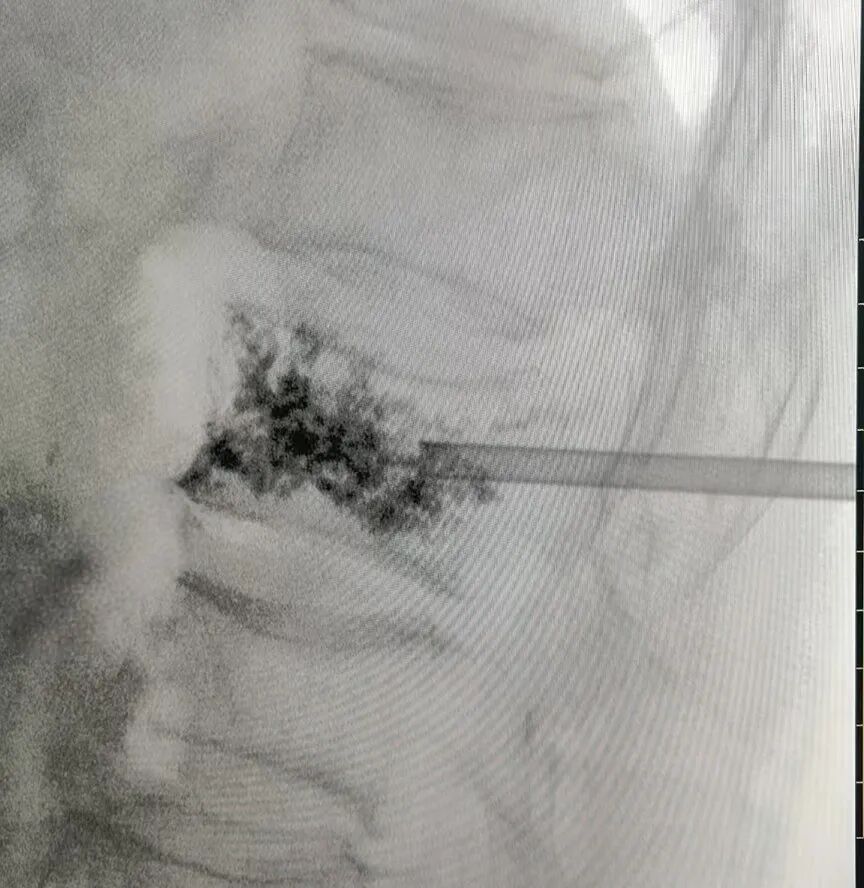

方奶奶入院后,骨科团队全面评估其心肺功能等指标,量身定制PKP手术方案。主治医师王亮在局部麻醉下通过微小切口,在影像精准引导下将穿刺针植入病变椎体,注入骨水泥加固,水泥弥散良好。整个过程耗时不到1小时,创伤小、出血少,术后无需长时间禁食。